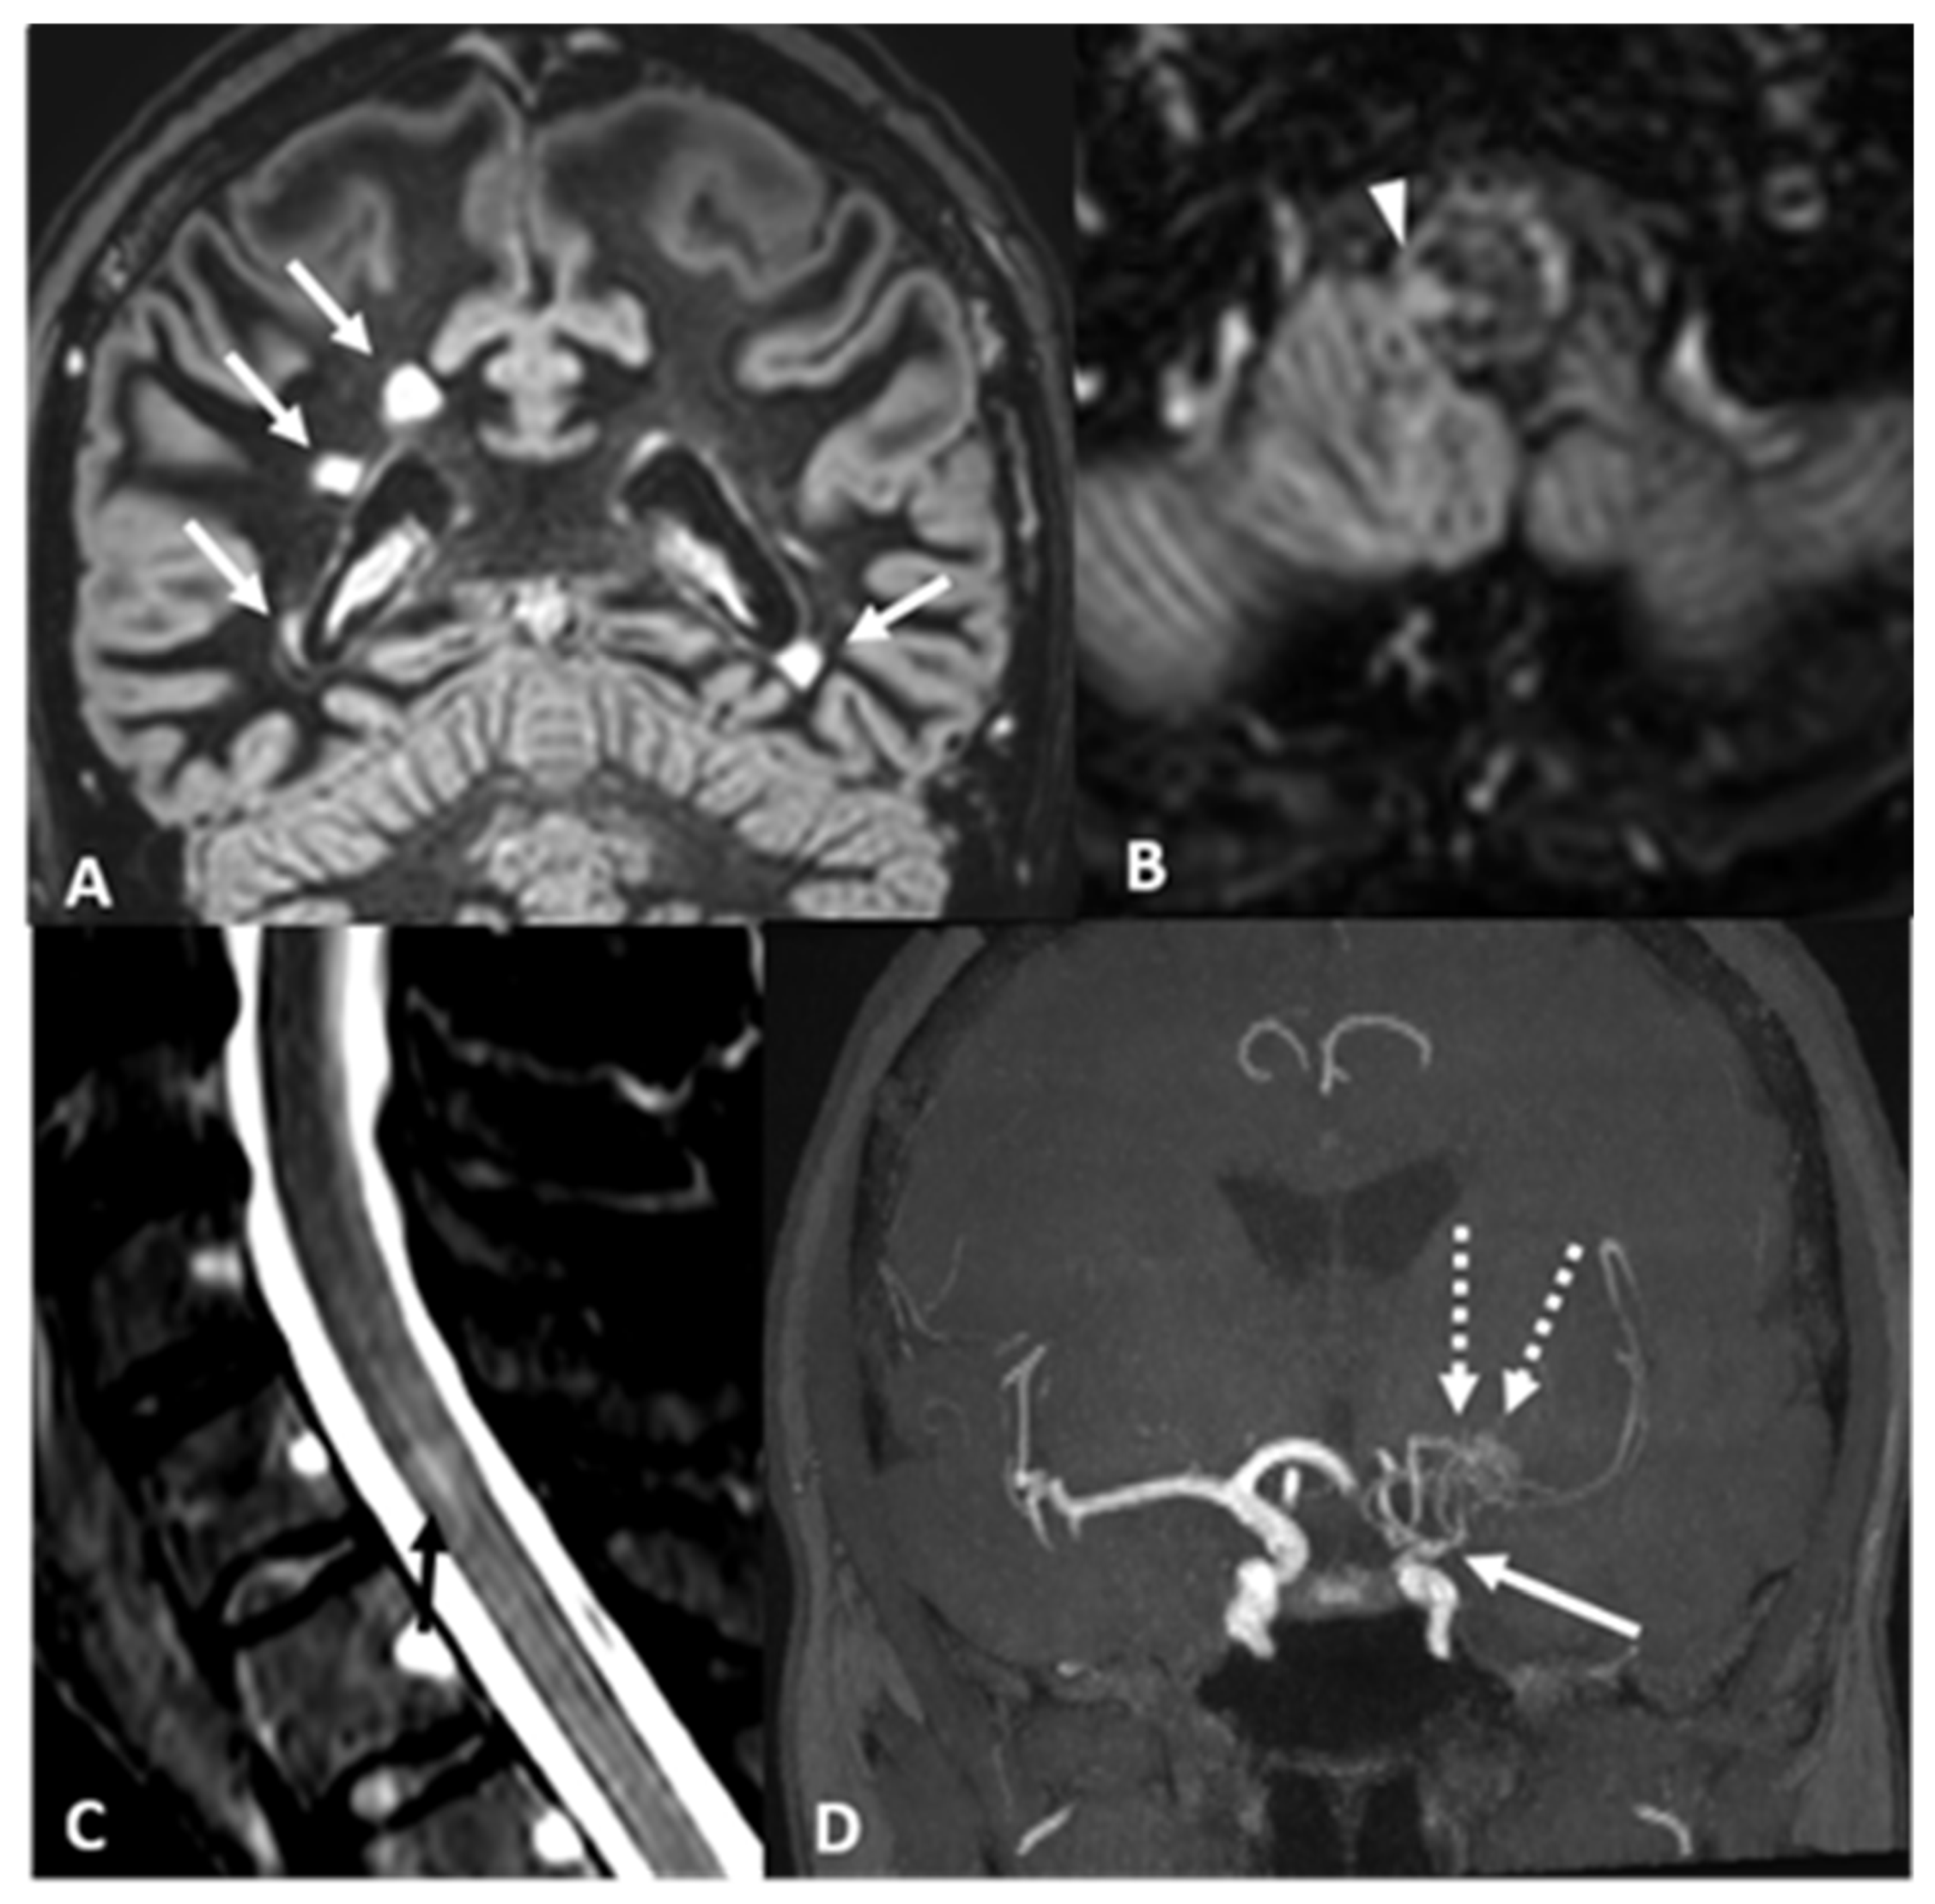

2.2. Case 2: A 43 Years-Old Woman Was Evaluated in Our Institute Because of the Neuroradiological Finding of Unilateral MMA

| Our Case 2 | Italy/ Caucasian | 43/F | Left hemi-anesthesia (transient, recurring) | Bilateral supratentorial periventricular with corpus callosum involvement, left cerebellar hemisphere; bulbospinal tract; cervical spine | Brain: − Spine: − | + | + | − | AntiAQP4 (−) Anti-ds DNA-ANA-ENA-ANCA-Anti cardiolipin and beta2GP(−) G20210A Factor II and MTHFRC1677T (heterozigosis) Total body PET (−) | Left MCA and distal ICA steno-occlusion, MM network | MMA + MS | no | Aspirin | Dimethylfumarate Glatiramer acetate Teriflunomide | 8 years |